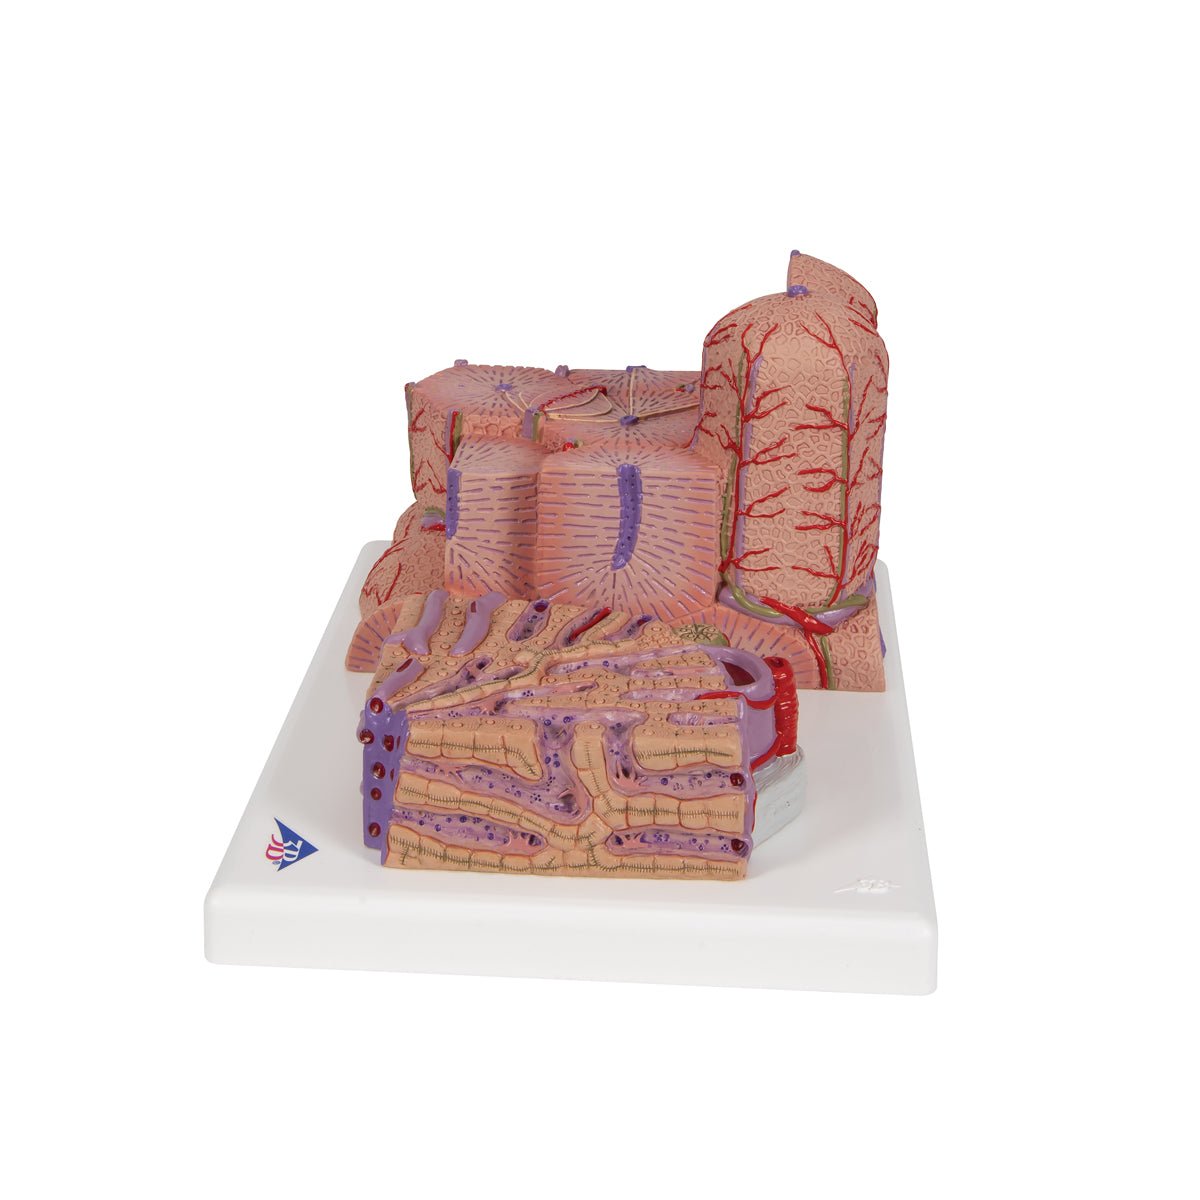

Salg af anatomiske modeller er det bærende element i eAnatomi, selvom vi også bruger mange ressourcer på at udvikle vores egne anatomiske materialer som fx plakater. Anatomiske modeller anvendes til forskellige formål og kan både vise afgrænset væv, organer samt organsystemer. Søger du en simpel model af knoglevæv eller måske en avanceret torso-model baseret på MRI teknologi, kan du finde det hele på eanatomi.com.